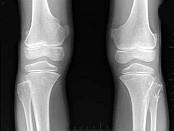

女,15岁,发现大腿远端肿块1周,无明显疼痛,结合图像,最可能诊断是?(?)A.骨质增生B.软骨瘤C.骨肉瘤D.骨瘤E.骨软骨瘤

问题 女,15岁,发现大腿远端肿块1周,无明显疼痛,结合图像,最可能诊断是?(?)

选项 A.骨质增生 B.软骨瘤 C.骨肉瘤 D.骨瘤 E.骨软骨瘤

答案 E